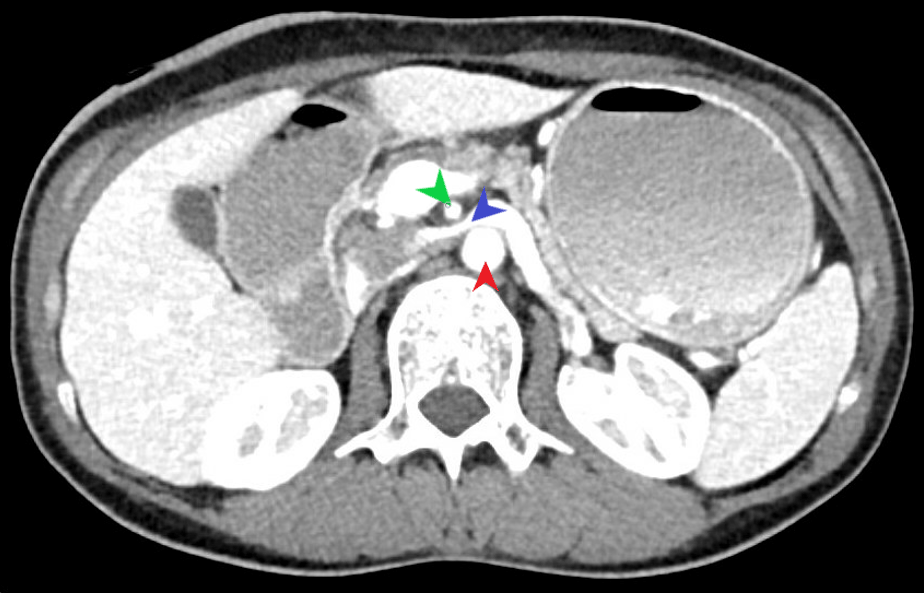

It is worthwhile to mention that SMAS can, at times, present alongside additional vascular compression syndromes. Most commonly, this being nutcracker syndrome (left renal vein compression between the SMA and AA) based on the anatomical location (Figure 2). Another example would be celiac axis compression syndrome which occurs due to compression of the celiac artery by the median arcuate ligament (1).